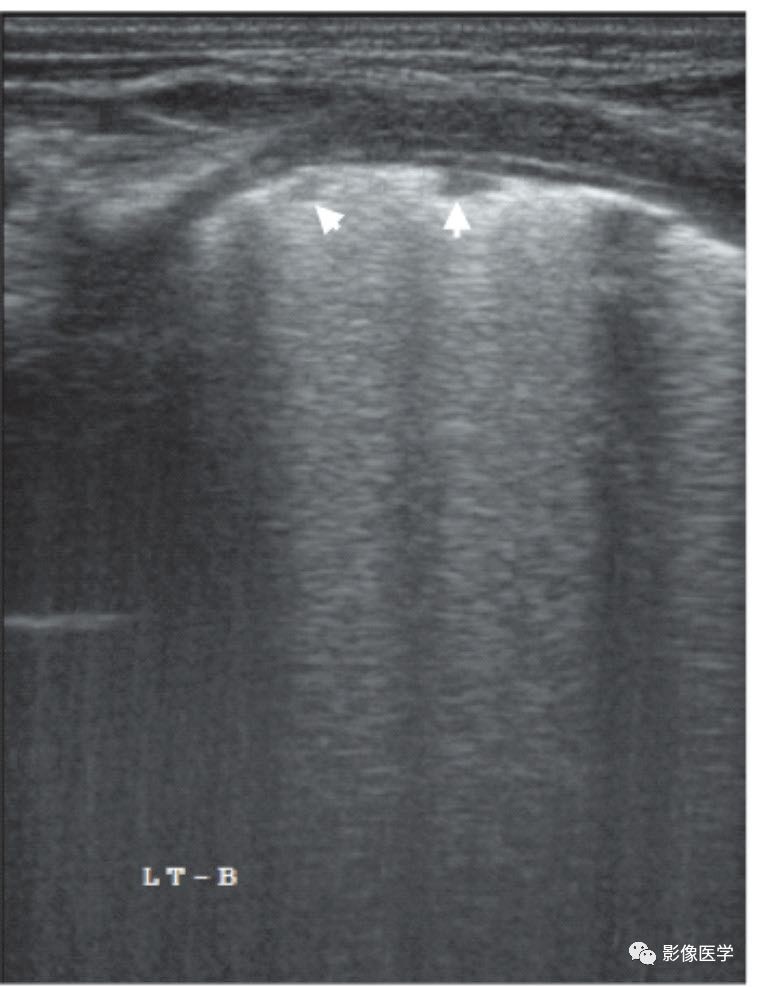

图6-20 乳汁吸入性肺炎:双肺点

胎龄32周,出生后28d,因胃食管反流致乳汁吸入。肺脏超声显示右肺明显实变伴支气管充气征,实变区边缘不规则,胸膜线消失或模糊;左肺未见实变,但可见明显双肺点(参见图6-21)。